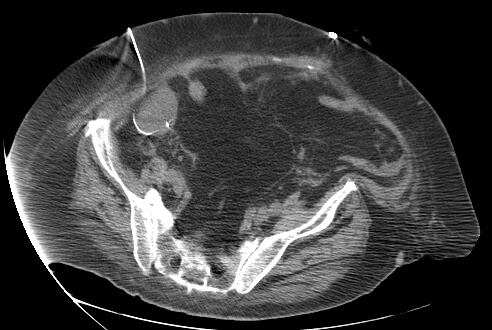

23 year old female with fever and RLQ tenderness s/p appendectomy.

Comment: This case demonstrates performance of a straight-forward CT-guided drainage. Once the abscess was localized on CT and the access site confirmed with a 25g needle, the collection was accessed with a Chiba needle and a guidewire was coiled within the collection. Serial dilatation was then performed so that a pigtail drainage catheter could be placed within the collection for drainage.